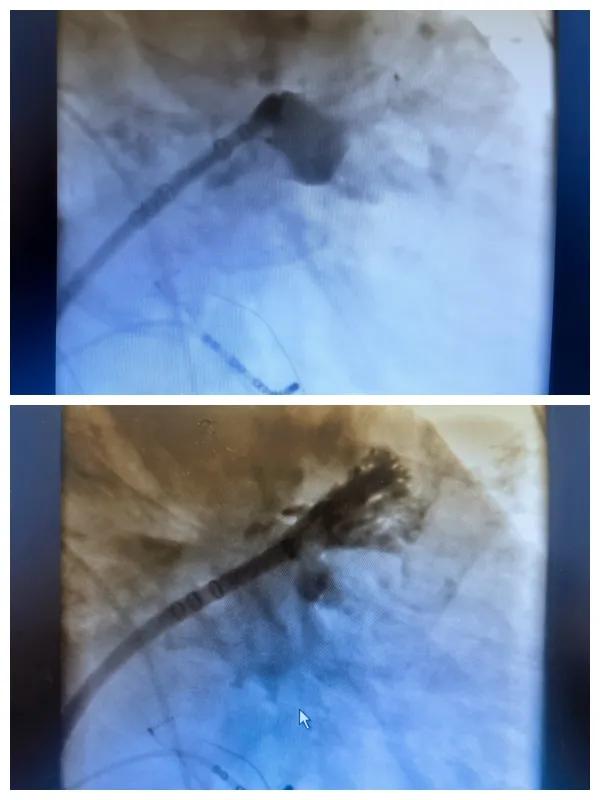

漯河市二院成功開展房顫射頻消融術+左心耳封堵WM FLX一站式手術,再攀“心”高峰!

房顫射頻消融術+左心耳封堵WM FLX一站式手術

6月26日,市二院成功為一名老年房顫患者實施了房顫射頻消融術+左心耳封堵WM FLX一站式介入治療,標志著醫院在心律失常介入治療領域邁出了嶄新的一步,開啟了新的治療篇章。

本次手術特邀我國著名心血管內科專家、河南省胸科醫院黨委書記袁義強及血管內科七病區主任黃瓊教授蒞臨指導,市二院院長王瑾帶領心血管內科電生理等專家團隊緊密合作,一次性解決了患者房顫、血栓兩大困擾,也使患者告別了終身服用抗凝藥的痛苦,極大地降低了患者的經濟和用藥負擔。

為了讓患者得到全面、綜合的治療,經過團隊術前充分討論,并征得家屬同意,心血管內科團隊決定采用目前國內外先進的房顫射頻消融術+左心耳封堵WM FLX一站式介入微創手術來治療老人的疾病。整個手術過程圓滿順利,術后何大爺各項體征正常,蘇醒后順利返回病房。